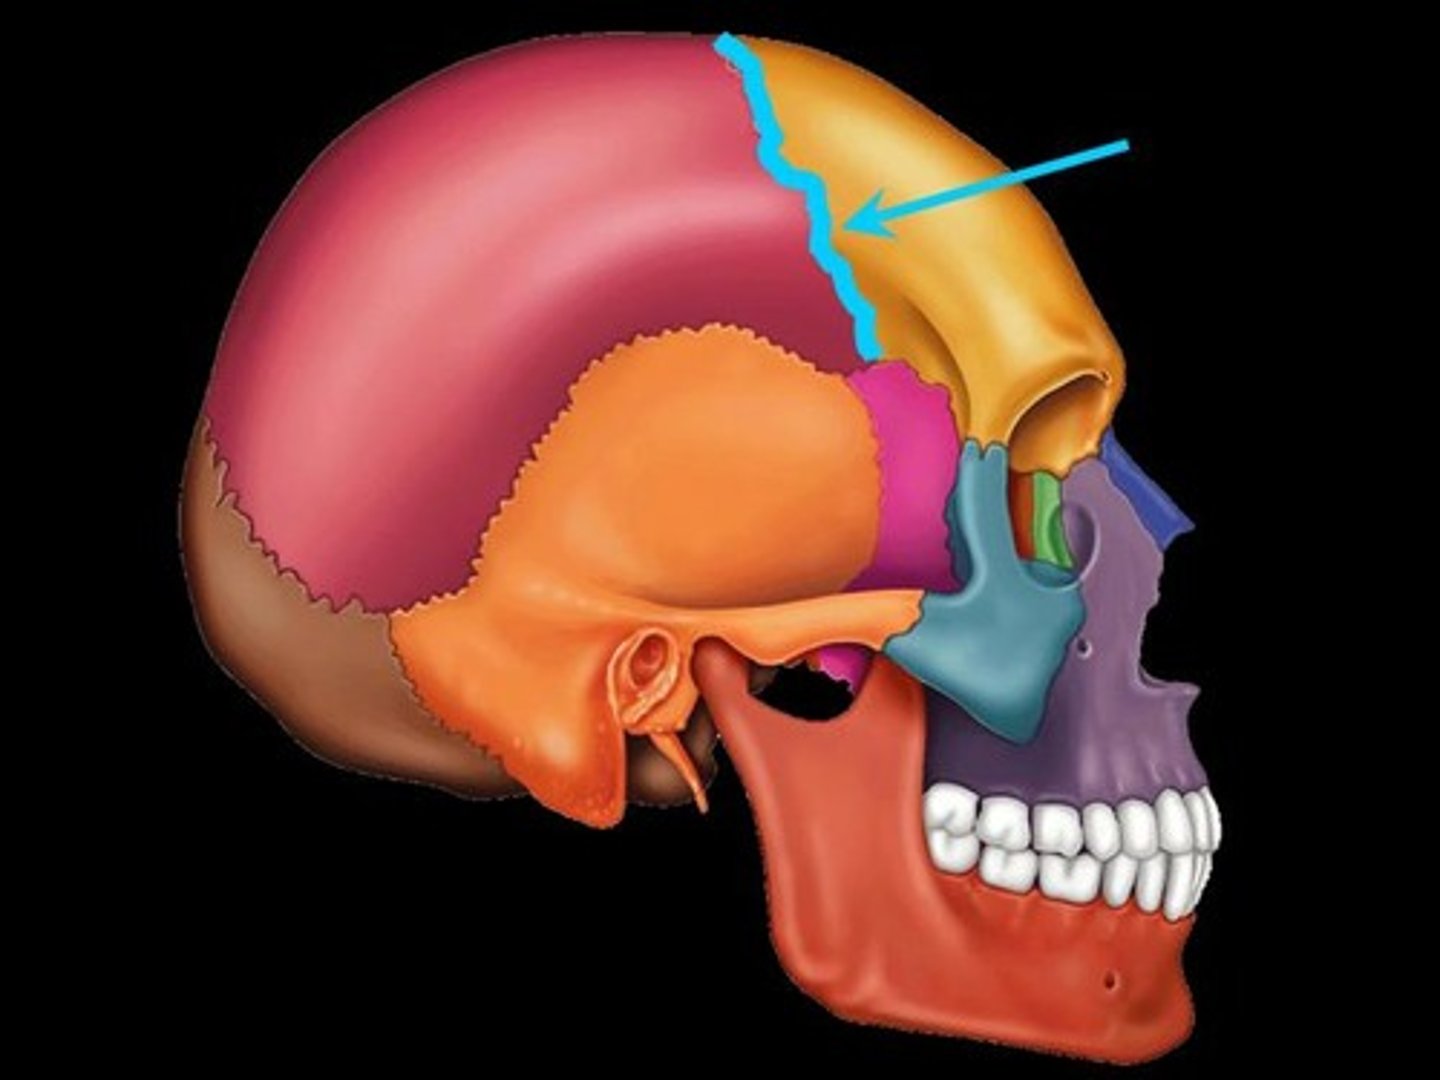

Parts of the Skull

Coronal Suture

Coronal Suture